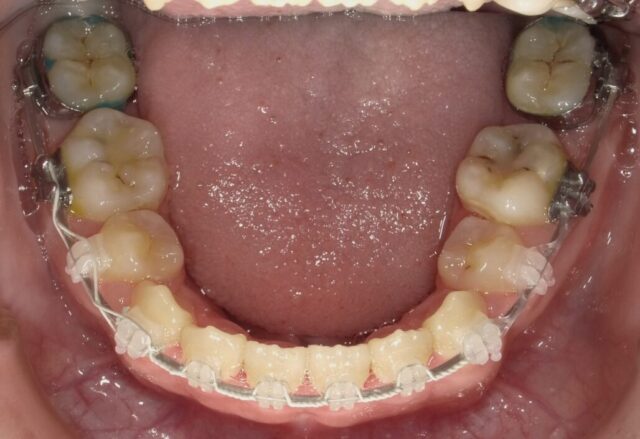

≪下顎咬合面観≫

2023年5月